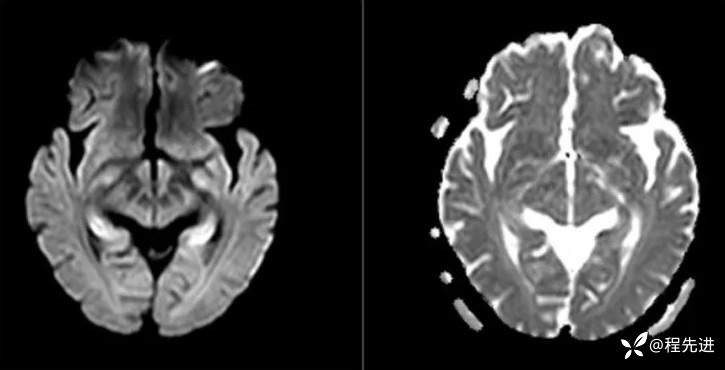

MRI平扫+增强:

DWI、ADC:

T1、T1增强: